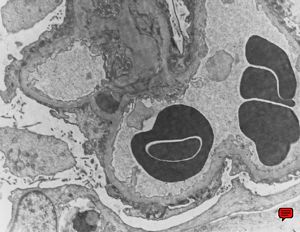

M,29y. | type II membranoproliferative glomerulonephritis (dense deposit disease)